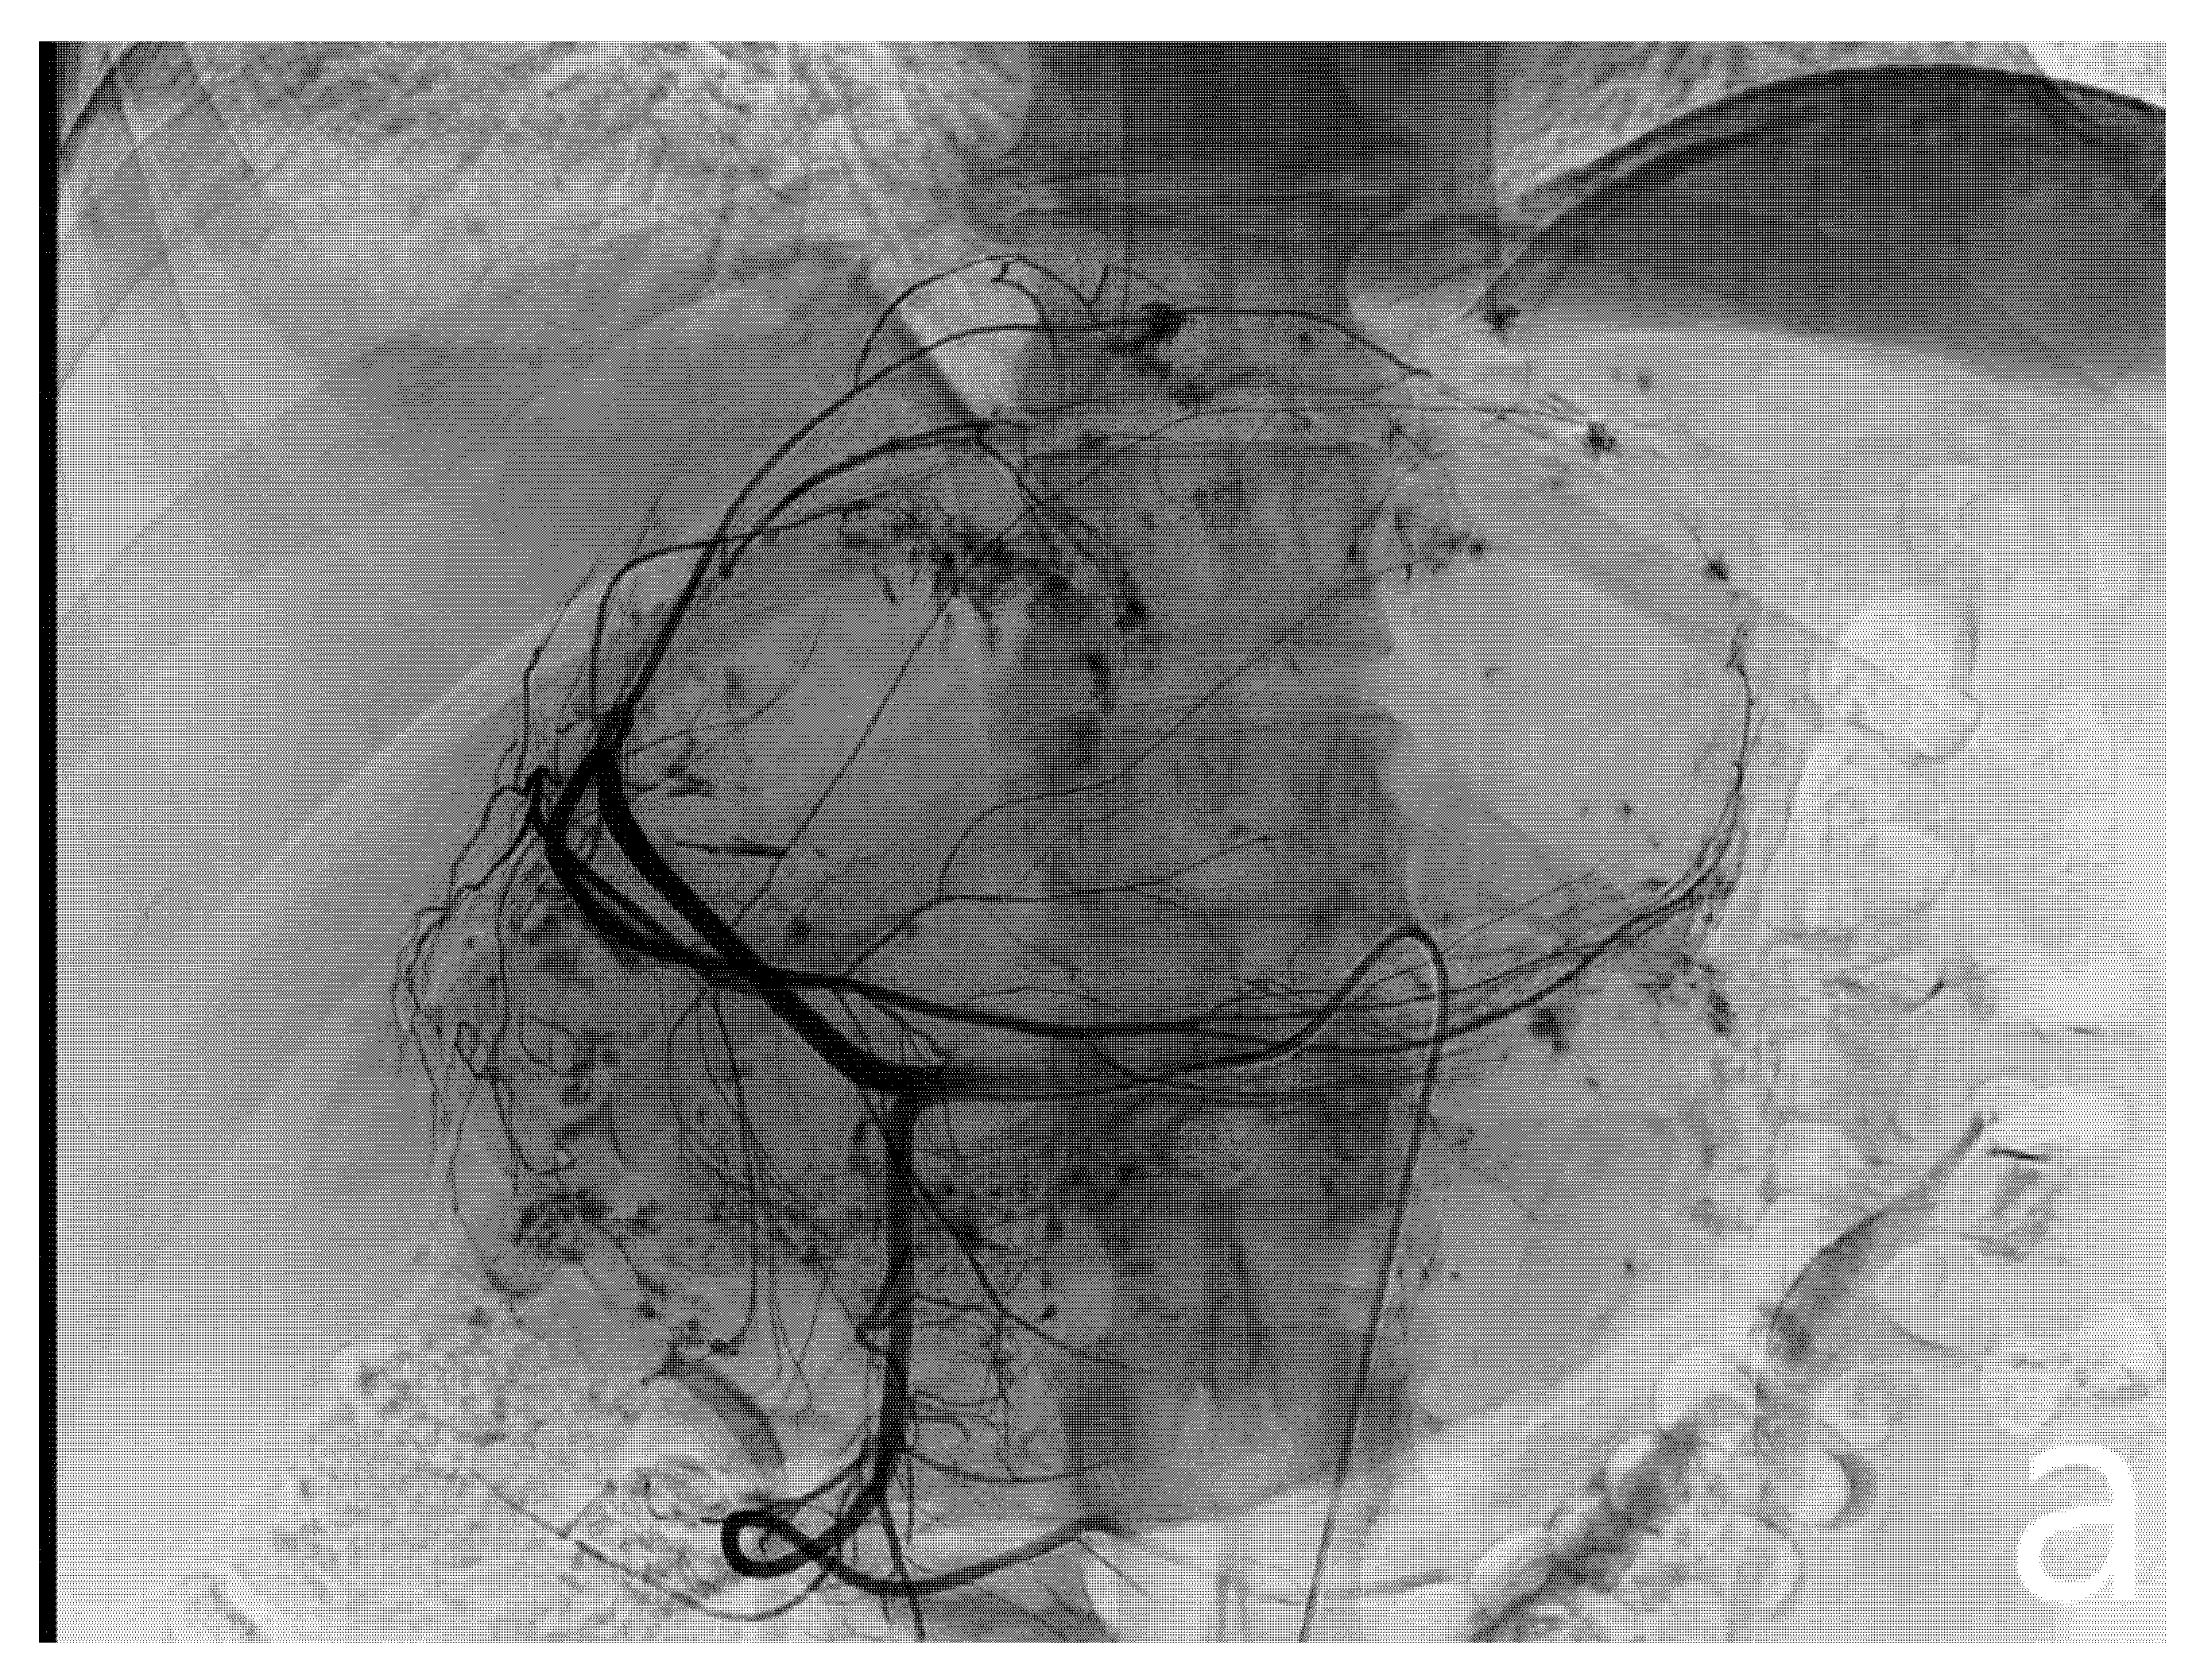

After confirmation of the feeding arteries, superselective catheterization of the single feeding vessel was obtained using a microcatheter (Boston Scientifics, Marlborough, MA, USA); embolization was achieved using polyvinyl alcohol particles (PVA), whose size varied, depending on the caliber of the feeding artery. In patients planned for major hepatectomies, whenever a wide feeding artery was identified, ethylene-vinyl alcohol copolymer (EVOH)-based liquid embolic agent (Squid Peri, Emboflu, Switzerland) was used to complete the embolization (Figure 2).

Figure 2.

Pre- and post-embolization angiography. A giant hemangioma with vascular afference from the left hepatic artery originating independently from the celiac trunk is identified (a). Embolization is performed with microparticles and Squid 18 to achieve complete lesion devascularization (b).